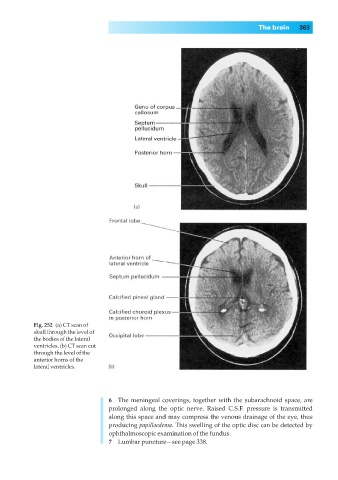

Fig. 252◊(a) CT scan of

skull through the level of

the bodies of the lateral

ventricles. (b) CT scan cut

through the level of the

anterior horns of the

lateral ventricles.